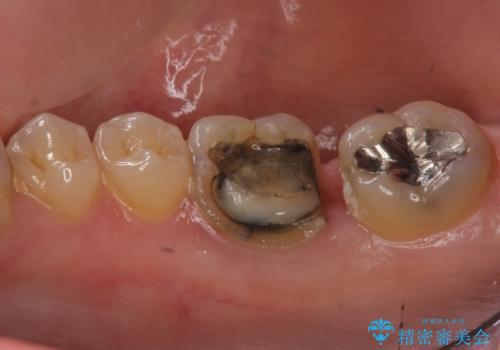

- 右下奥歯の詰め物が取れたとのことで来院されました。

セラミックでの治療をご希望されましたが、残っている歯が少なかったためクラウンでの治療を行いました。

もう一つ奥の歯に関してもセラミックにやり替えたいとのことでしたので、こちらはインレーでの治療を行いました。